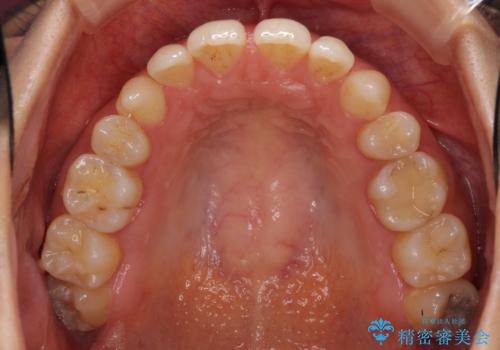

- 以前の矯正治療の後戻りにより、上の前歯にスペースができたことを気にして来院された患者様です。

インビザラインを用いて前歯のスペースを閉じつつ、上下の咬み合わせを構築していくこととしました。

隙間の空いてしまった前歯は、矯正治療で治療を行っても後戻りが起こりやすい傾向にあります。

マウスピースの保定装置をしっかりと装着しても空いてしまうため、細いワイヤーによる保定を併用することで後戻りを防止しています。